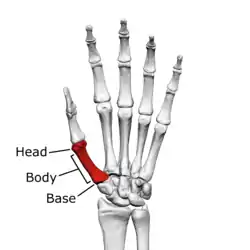

![]() First metacarpal of the left hand (shown in red). Palmar view. | |

The first metacarpal bone or the metacarpal bone of the thumb is the first bone proximal to the thumb. It is connected to the trapezium of the carpus at the first carpometacarpal joint and to the proximal thumb phalanx at the first metacarpophalangeal joint.

The first metacarpal bone is short and thick with a shaft thicker and broader than those of the other metacarpal bones. Its narrow shaft connects its widened base and rounded head; the former consisting of a thick cortical bone surrounding the open medullary canal; the latter two consisting of cancellous bone surrounded by a thin cortical shell. [1]

Head

The head is less rounded and less spherical than those of the other metacarpals, making it better suited for a hinge-like articulation.

The distal articular surface is quadrilateral, wide, and flat; thicker and broader transversely and extends much further palmarly than dorsally. On the palmar aspect of the articular surface there is a pair of eminences or tubercles which articulate with the radial and ulnar sesamoid bones of the thumb metacarpophalangeal joint; the lateral eminence is larger than the medial.

Body/Shaft

The body or shaft is thick and broad — averaging 6 to 11 millimetres (0.24 to 0.43 in). On its dorsal side, the shaft is flat and wide, while the anteroposterior side is less pronounced; usually resulting in an oval-triangular cross-section.

The dorsal surface of the shaft is weakly convex longitudinally, while its palmar, radial, and ulnar surfaces tend to be concave. The palmar and medial surface exhibits a blunt ridge which separates a larger lateral part – the insertion of the opponens pollicis muscle – and a smaller medial part – the origin of the lateral head of the first dorsal interosseous muscle.

Base

The base is significantly different from the bases of the other metacarpals. It is trumpet-shaped and ends in a saddle-shaped articular surface matching that of the trapezial articular surface. The configuration of the thumb carpometacarpal joint plays an important role in the mechanism of opposition. The articular surface is delimited by a thick, crest-like ridge extending around its circumference.

On the palmar and lateral side of the base is the insertion of the tendon of the abductor pollicis longus muscle, usually featuring a small tubercle. The origin of the first dorsal interosseous muscle is on the ulnar aspect of the base, and can sometimes extend onto the shaft. In contrast to the other metacarpals, the first metacarpal has no articular facets on the sides of its base (for intermetacarpal articulations) because it articulates exclusively with the trapezium.